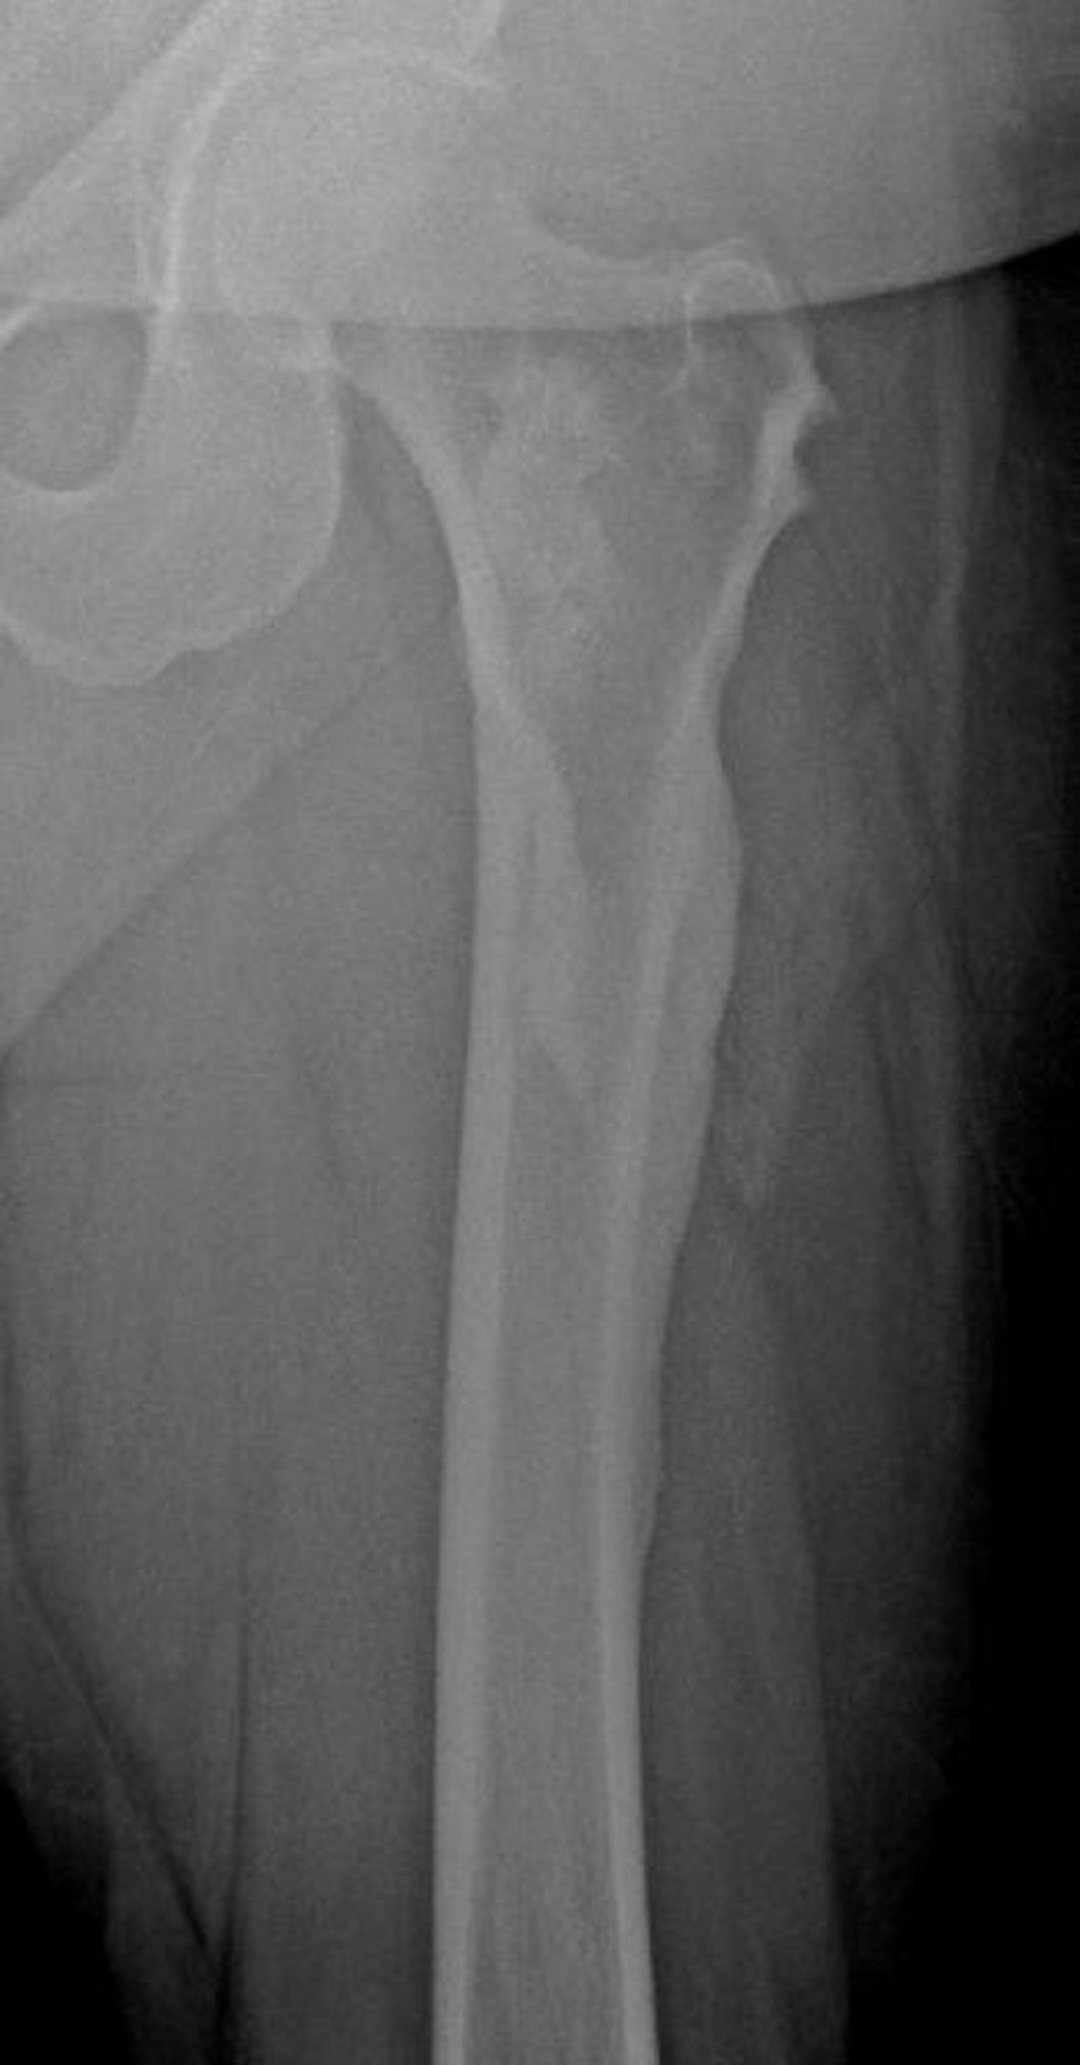

Мелореостоз (вид капающего воска свечи)

На данной рентгенограмме представлен характерный для мелореостоза вид в форме «стекающего воска свечи» в области бедренной кости; он особенно выражен на латеральной кортикальной поверхности бедра.